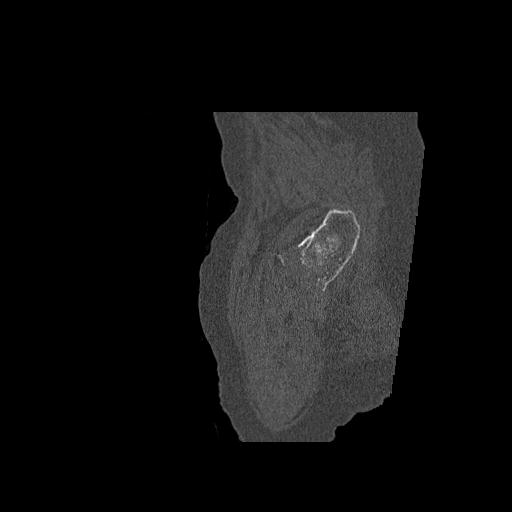

49554 3/13 膝 4R 3/16 4R 1/18 2R 78歳男性 膝蓋骨骨折